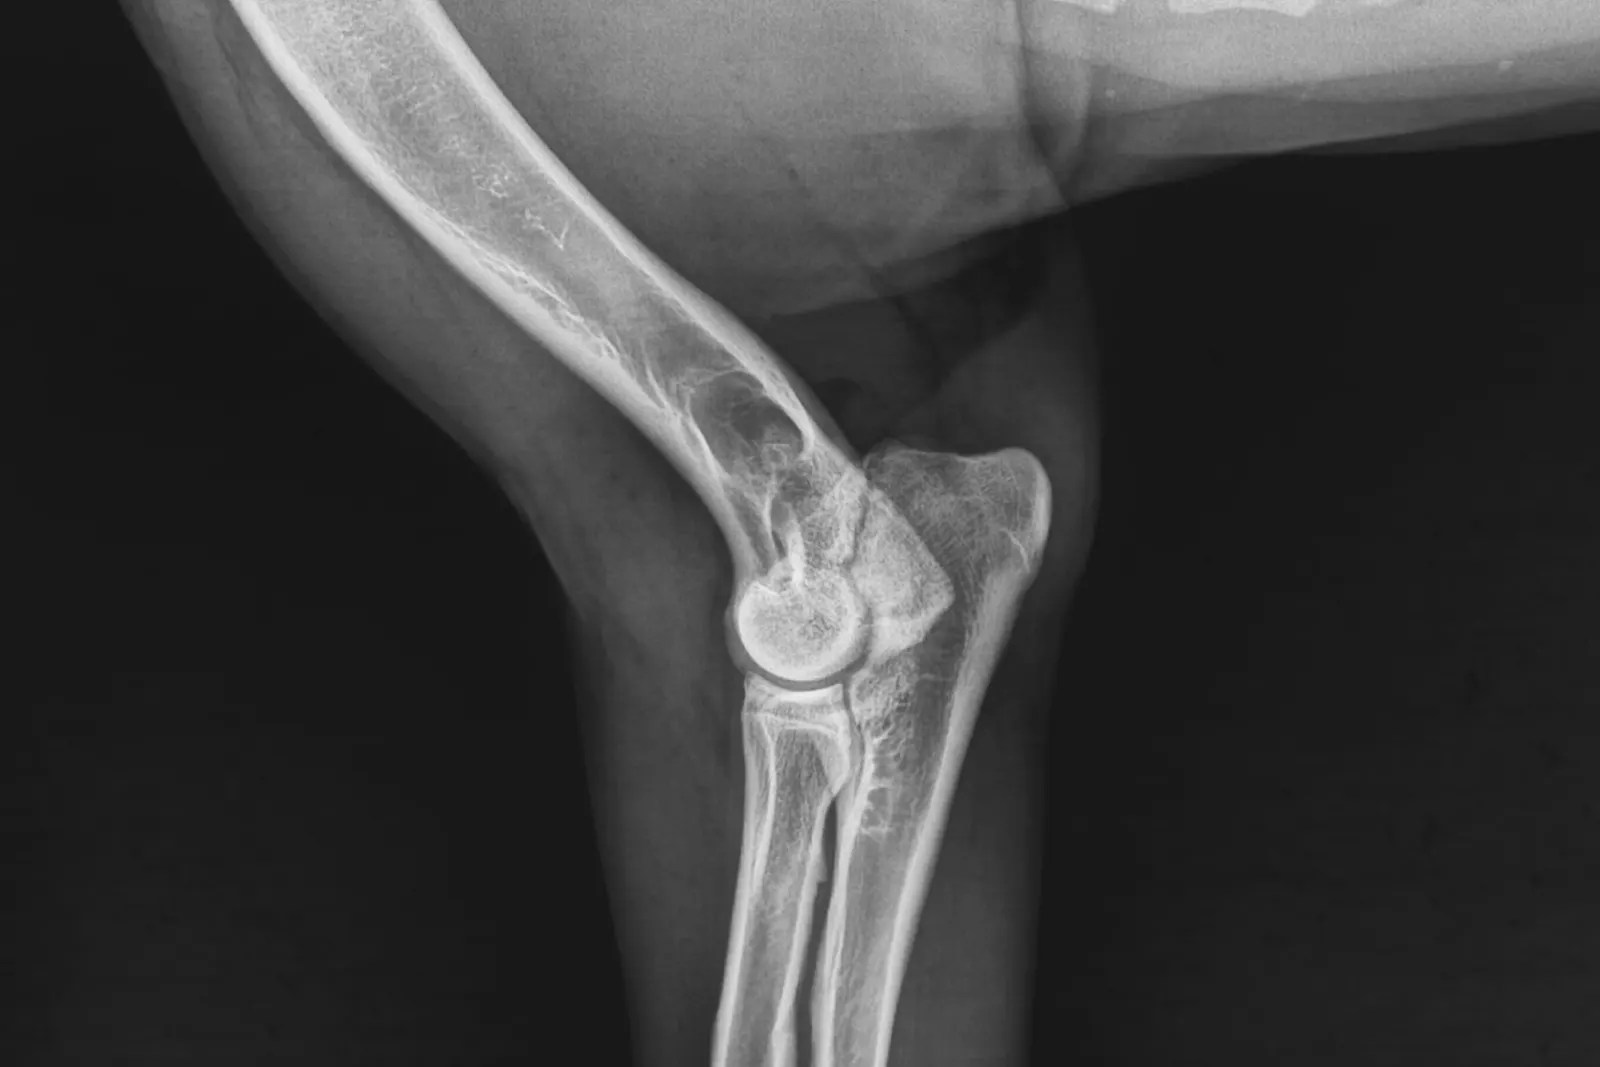

Kod nekih pasa mehanički nedostaci rezultiraju traumom drugih struktura u zglobu, kao npr. meniskusa (hrskavice koja apsorbira udarce). Kada bedrena kost klizi niz kosinu tibije, može oštetiti tu hrskavicu, posebno središnju stranu. Dijagnoza rupture prednjeg križnog ligamenta obično se postavlja tijekom ortopedskog pregleda, odnosno specifičnih testova za koljeno.

Kod pasa s djelomičnim puknućem ili ranom degeneracijom ligamenta potrebno je RTG snimanje ili magnetska rezonanca (u sedaciji). Kod većine pasa se koristi i eksplorativna artroskopija za potvrdu dijagnoze i procjenu stanja hrskavice. Konzervativno liječenje ove bolesti se rijetko preporučuje, osim u slučajevima rizične opće anestezije.